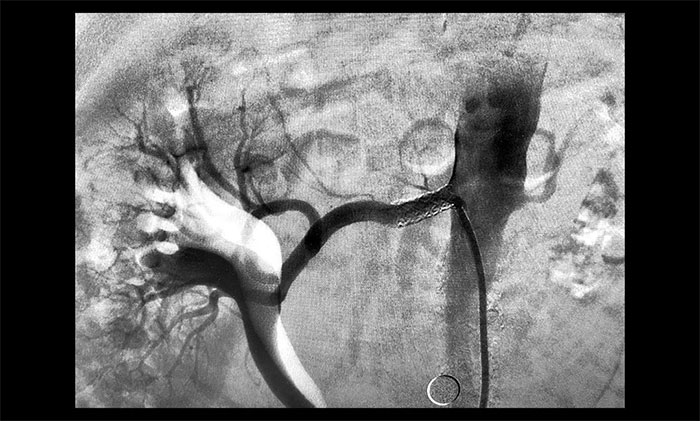

血压居高不下竟是肾动脉狭窄“惹祸” 医院成功开展肾动脉狭窄支架置入手术

肾动脉狭窄是引起高血压和(或)肾功能不全的重要原因之一,若不及时治疗,病情会持续恶化。近期,医院学术副院长、神经内科4A病区主任席刚明教授带领团队顺利开展一例肾动脉狭窄支架置入手术,保护岌岌可...【详细】